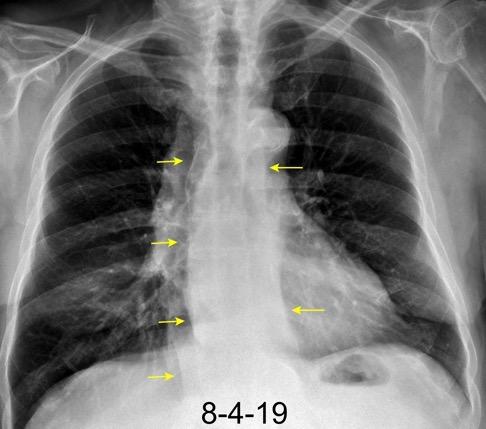

Ganglios retroperitoneales (flechas negras)

germinales del testículo izquierdo Nódulos pulmonares múltiples. (flechas verdes). Ganglios paratraqueales. (flechas amarillas). Dudoso ensanchamiento retrocrural (flechas negras)

Panda A et al. “Straddling Across Boundaries”. Thoracoabdominal Lesions: Spectrum and Pattern Approach. Curr Probl Diagn Radiol, 2015